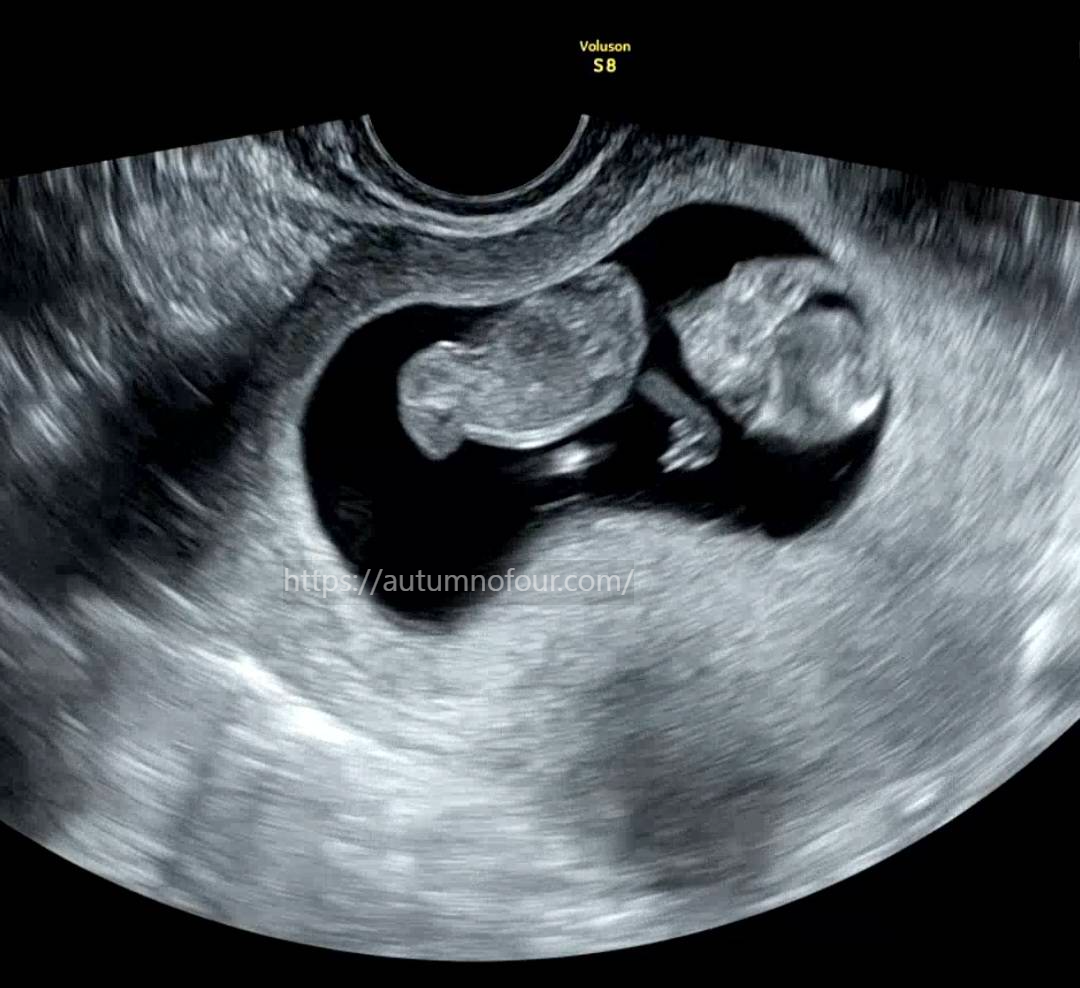

초음파를 보는데 억?? 소리가 나왔다

고새 어떻게 이렇게 많이 큰거지??????

지난번엔 팔과 다리가 정말 젤리곰 같이 찔끔(?) 나와있었는데

아주 쭈-------욱 하고 늘어나있었고,

그 덕분인지 꼬물꼬물 움직이는게 정말 잘 보였다.

손가락도 보이고, 사람형태가 된 44MM 아가 ㅋㅋㅋㅋㅋ